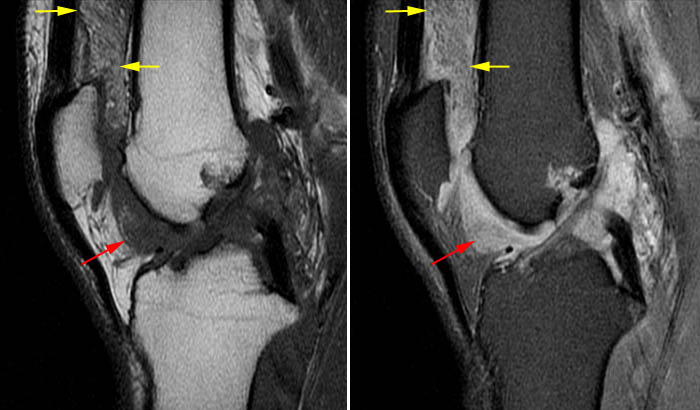

Супрапателлярный импиджмент коленного сустава: симптомы и лечение